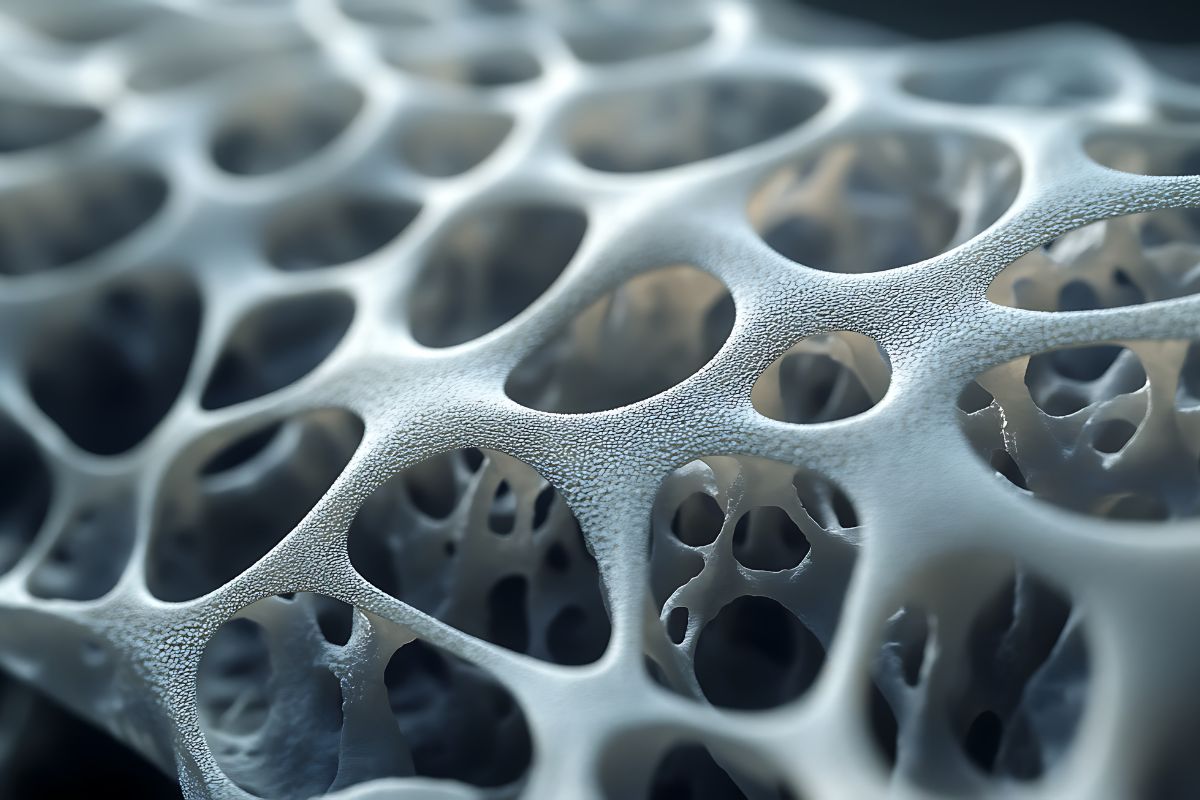

Também é frequente a formação de cálculos renais, alteração da função renal e a redução da densidade óssea, com risco aumentado de osteoporose e fraturas.

No hiperparatireoidismo, a abordagem pode incluir acompanhamento clínico, uso de medicamentos para controle do cálcio e, em muitos casos, tratamento cirúrgico para remoção do adenoma ou das glândulas acometidas. A decisão cirúrgica é baseada em critérios bem estabelecidos, como idade, níveis de cálcio e presença de complicações como osteoporose e cálculo renal.

No hiperparatireoidismo, o objetivo principal do tratamento é reduzir os níveis elevados de PTH e de cálcio no sangue, prevenindo complicações como osteoporose, fraturas, cálculos renais e prejuízos à função renal.

A indicação cirúrgica segue critérios bem definidos, como idade abaixo de 50 anos, hipercalcemia persistente, presença de osteoporose, histórico de cálculos renais ou redução da função renal.